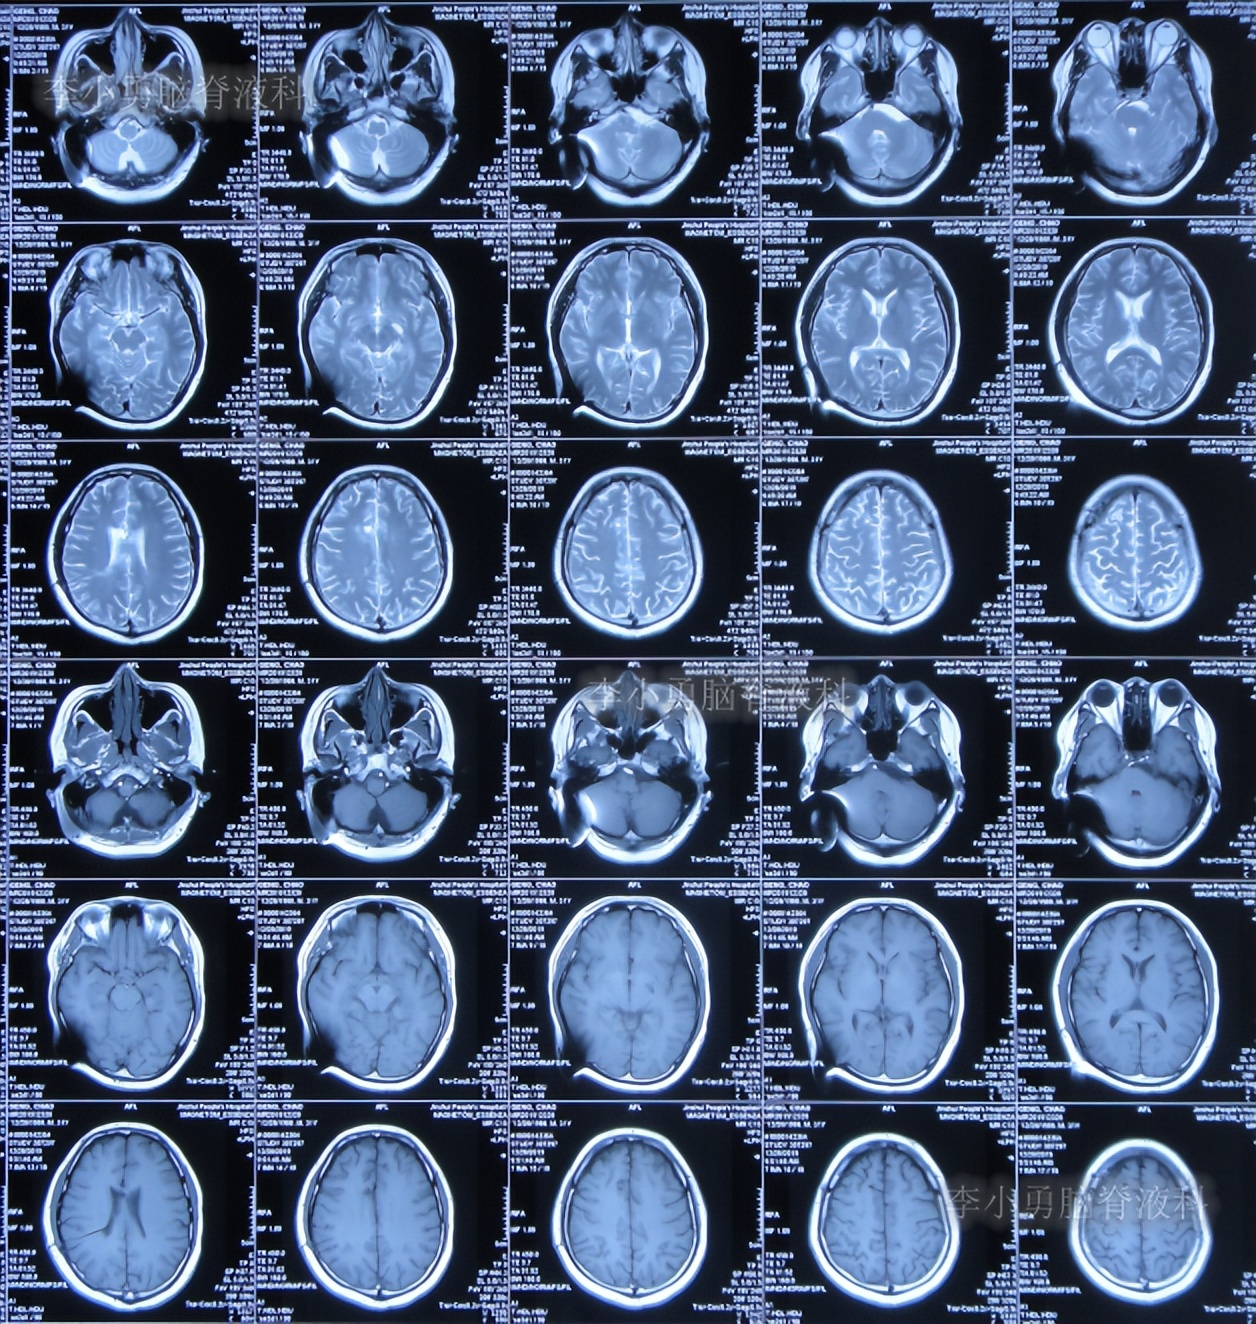

图-2:2019年10月5日头颅核磁

图-5:2019年12月28日头颅核磁

图-10:2020年2月9日头颅核磁

图-11:2020年2月13日头颅核磁